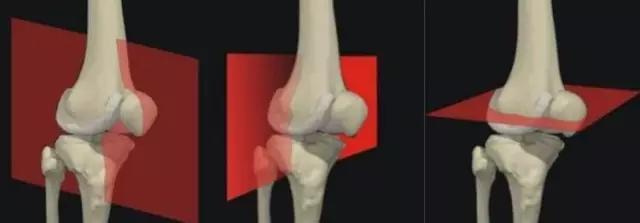

阅读MRI的过程——

单一的指征(坐标)极其容易误漏诊!同一截面发现的特征(坐标)越多越好,还要得到不同截面的图像来佐证。除了MRI的表现外,年龄、性别、病史、症状、体征等均应该是诊断的坐标!